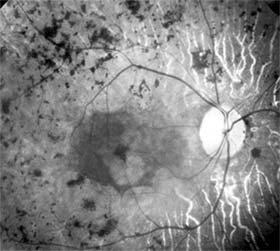

Retinitis pigmentosa is a group of hereditary retinal degenerations characterized by progressive dysfunction of the photoreceptors and associated with progressive cell loss and eventual atrophy of several retinal layers. The typical form of this disease can be inherited as an autosomal recessive, autosomal dominant, or X-linked recessive trait; one-third of cases will have a negative family history. The hallmark symptoms of retinitis pigmentosa are night blindness (nyctalopia) and gradually progressive peripheral visual field loss. The most characteristic ophthalmoscopic findings are narrowing of the retinal arterioles, mottling of the retinal pigment epithelium, and peripheral retinal pigment clumping, referred to as "bone-spicule formation" (Figure 10-19). While retinitis pigmentosa is a generalized photoreceptor disorder, in most cases rod function is more severely affected, leading to subjective sensations associated with poor scotopic function. The electroretinogram usually shows either markedly reduced or absent retinal function; the electro-oculogram lacks the usual light rise. The fundus appearance of retinitis pigmentosa may be mimicked by several disorders, including chorioretinitis, trauma, vascular occlusion, and resolved retinal detachment.

Figure 10-19

Figure 10-19: Retinitis pigmentosa with arteriolar narrowing and peripheral retinal pigment clumping.